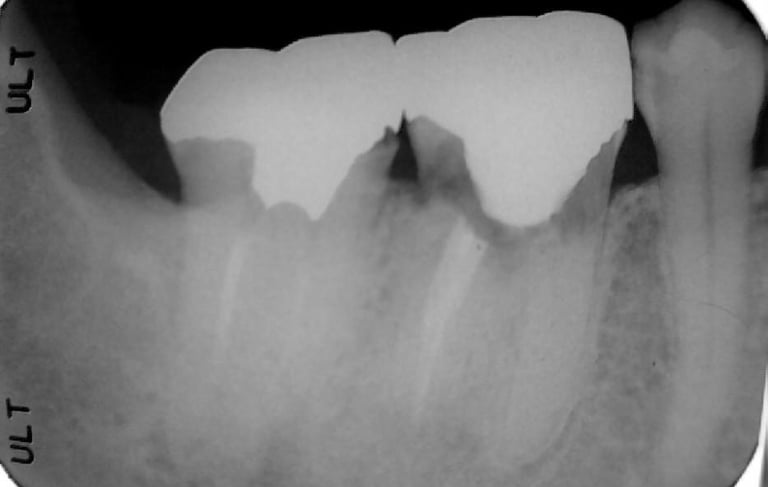

Se identifica si hay fracturas en la raíz del diente, que pueden causar dolor, infecciones o problemas de estabilidad dental. Se utilizan radiografías y exámenes clínicos para este diagnóstico.

Evaluación de fracturas radiculares

Diagnóstico de reabsorción radicular